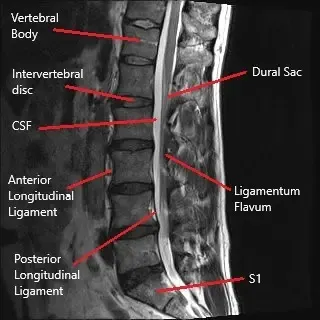

La columna lumbar consta de cinco vértebras (L1-L5) separadas por discos intervertebrales. Estos discos actúan como amortiguadores para absorber los golpes y permitir el movimiento. La médula espinal pasa por el canal central, y las raíces nerviosas se ramifican desde la médula espinal, saliendo de la columna vertebral a través del foramen intervertebral. Estos nervios controlan la sensación y el movimiento en la parte inferior del cuerpo. Una hernia discal puede comprimir estas raíces nerviosas, provocando síntomas como dolor, hormigueo y debilidad.

- Resonancia magnética (RM): La herramienta más eficaz para visualizar tejidos blandos como discos y raíces nerviosas. Puede confirmar hernia discal y compresión nerviosa.